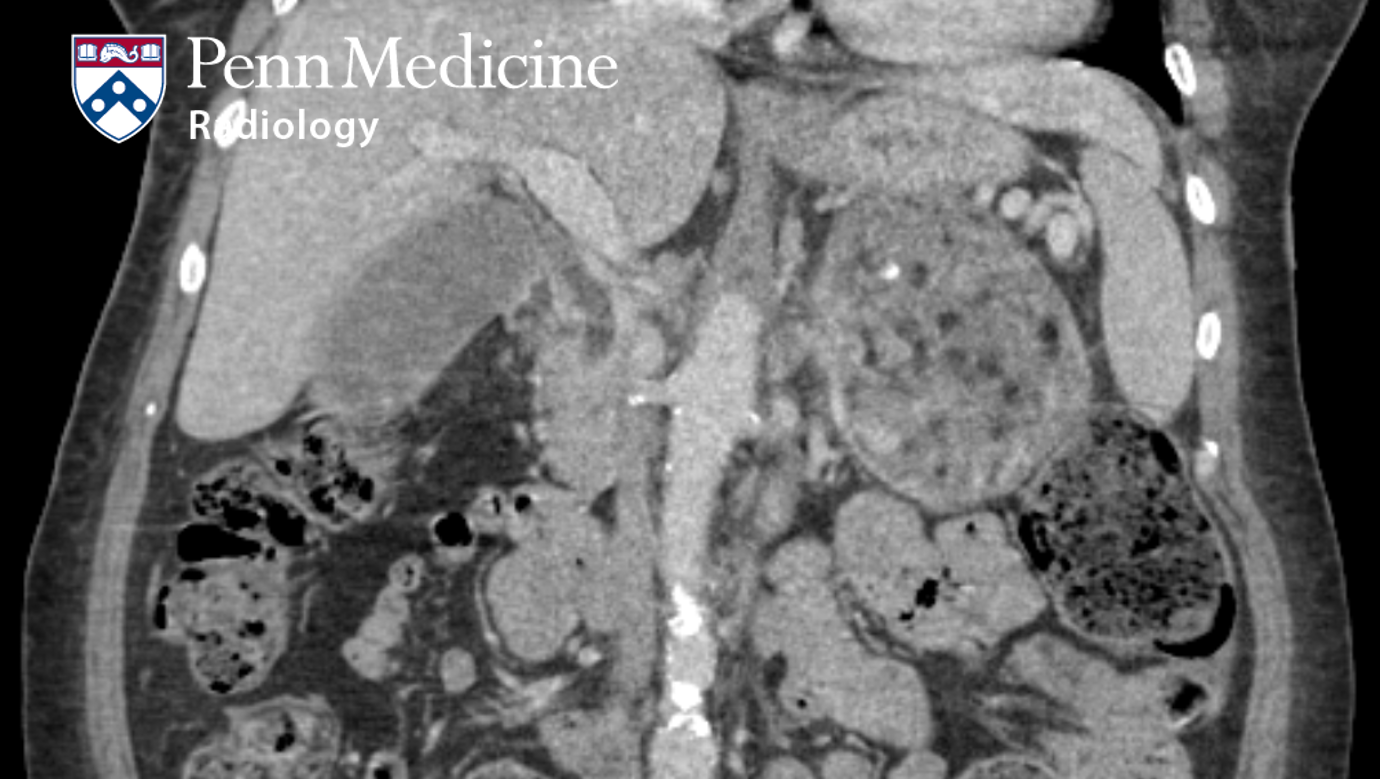

40-year-old man with an incidental adrenal mass

A 40-year-old man with weight loss and right-sided abdominal pain received an enhanced CT abdomen and pelvis, which demonstrated a focal colonic mass …